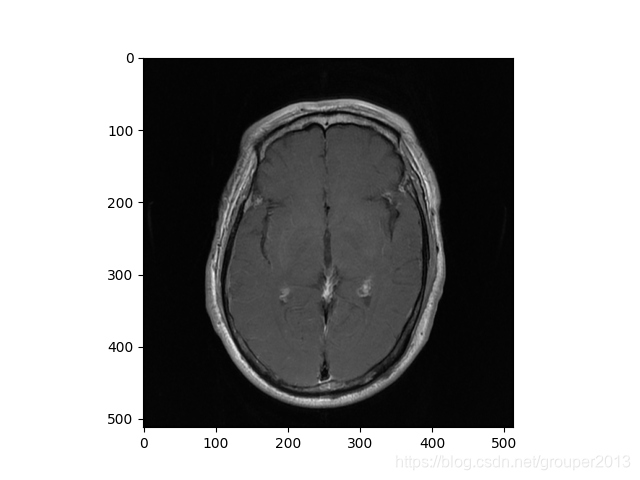

plt.imshow(pix,'gray') #显示图像

结果显示: